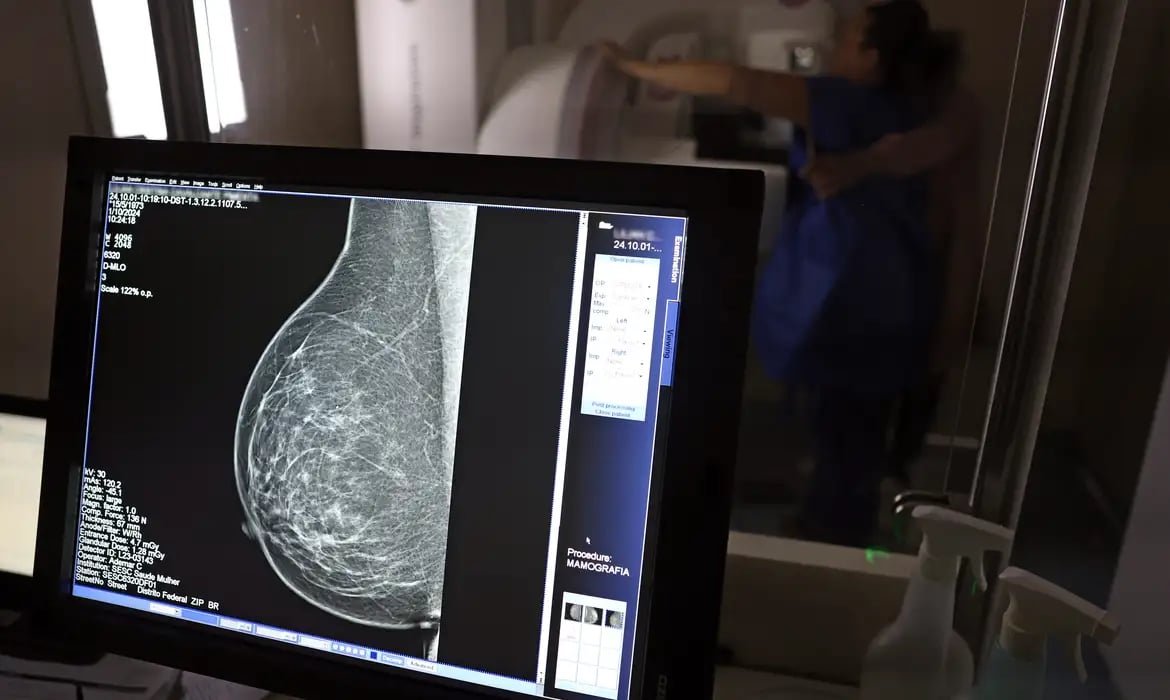

- Quais são os tipos de câncer de mama?